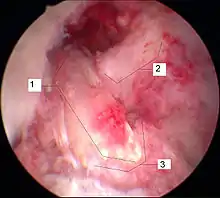

Arthroscopie

L'opération proprement dite commence par l'introduction de l'arthroscope dans le genou du patient. Ceci permet de confirmer définitivement le diagnostic de rupture de LC. Les autres blessures, en particulier celles des ménisques, peuvent être soignées avant la reconstruction du LC.